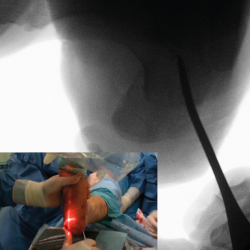

Figura 7. Imagen fluoroscópica de la traslación de la tuberosidad con un periostotomo (imagen anteroposterior) y su correspondencia en cirugía.

Figura 8. Imagen fluoroscópica de la traslación de la tuberosidad con un periostotomo (imagen axial) y su correspondencia en cirugía.

Figura 9. Imágenes fluoroscópicas de fijación de la osteotomía con agujas de Kirschner y tornillos canulados en anteroposterior y axial del calcáneo.